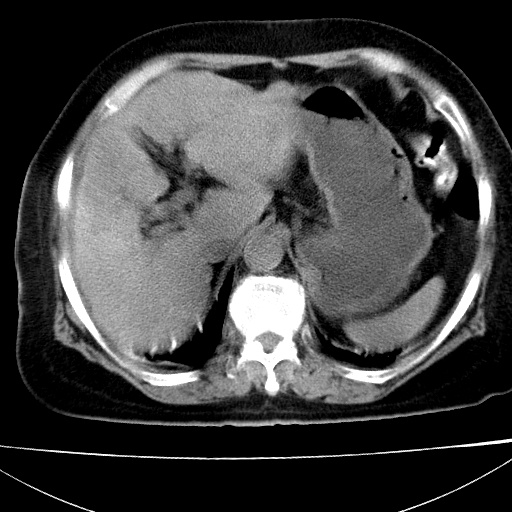

患者女74岁;右上腹胀痛1月,伴恶心,无发热;生活在疫水区。有术后病理及术后半年的追踪ct.

1)慢性血吸虫病(典型)。2)肝硬化。3)肝癌?4)胆囊炎。5)少量腹水。6)右侧少量胸腔积液。

支持.边缘见高密度线条样钙化影.

肝脏体积缩小,肝裂增宽,边缘不平呈波浪状,肝右叶见分隔状条索形钙化,亦见多结节低密度灶,边界不清,肝周可见少许液性暗区,胆囊增大内密度均匀,脾脏下缘低于脏脏的下缘,胸腔亦见液性暗区,余未见明显异常.

诊断:1肝硬化并慢性吸血虫病,脾肿大

2肝内占位,考虑肝癌可能性大,建议做增强

3胆囊炎, 4少量腹水及胸水

胆囊增大饱满,壁增厚。胆囊颈部见软组织密度影。临近肝右叶前段见片状低密度区,病灶下部见条状钙化,少量胸腹腔积液。意见:胆囊颈癌累及肝脏。